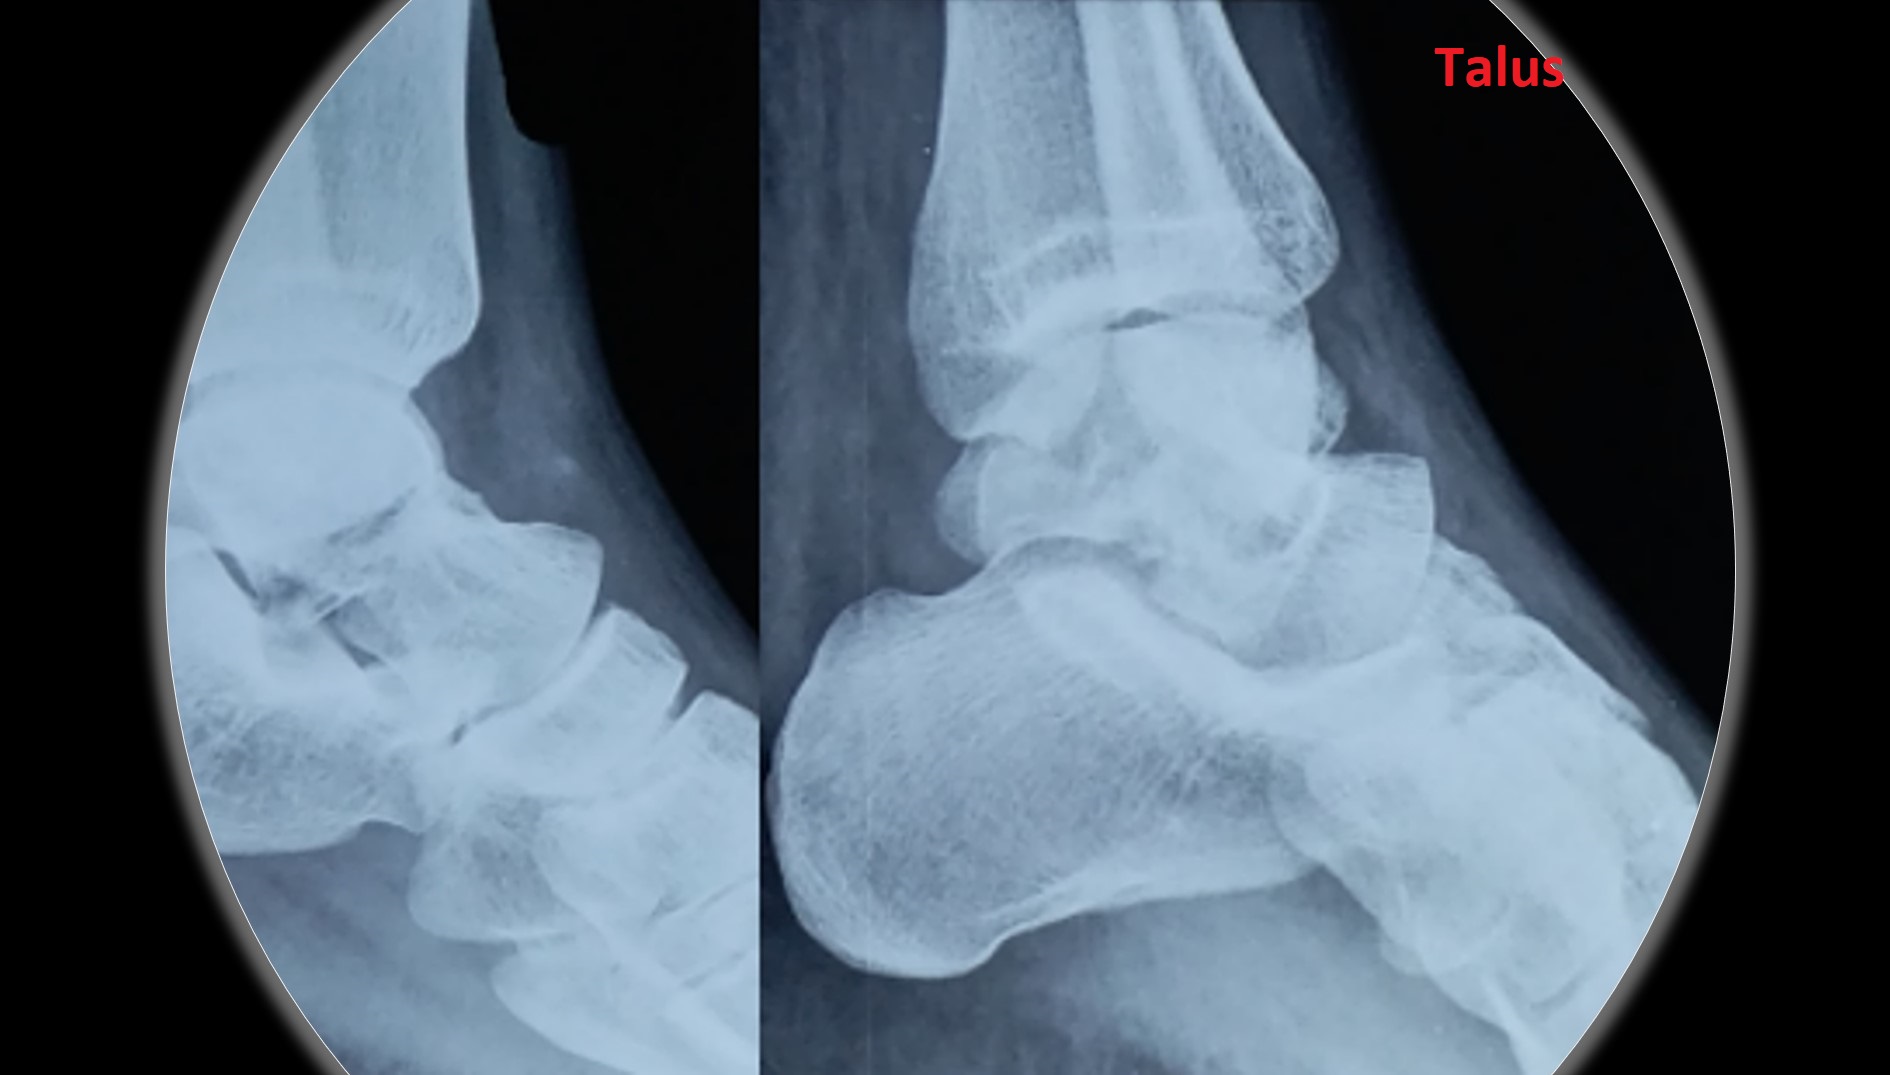

CRPP ( Closed Reduction Percutaneous Pinning )

• It can be applied to any intraarticular fractures, distal end radius, elbow, ankle and foot.

• PCCS (Percutaneous Cannulated Cancellous Screws) can be added to CRPP, when interfragmentary compression is a must.